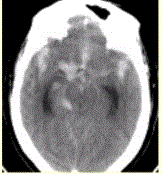

问题 患者男,50岁,突发昏迷、呕吐1h。查体:颈项强直,脑膜刺激征阳性,CT表现如图1。 进一步确诊蛛网膜下腔出血的病因,应首选

选项 A.CTA B.MRA C.MRI D.MRI增强 E.CT增强

答案 A